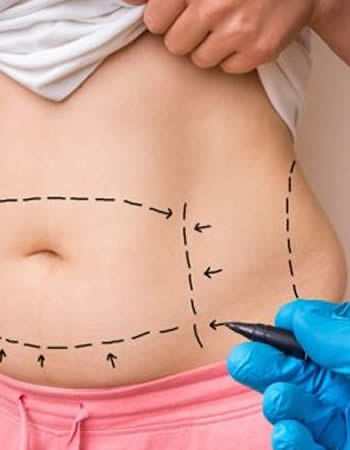

Más Detallescirugía postbariátrica en Ecuador

¿Qué es la Cirugía Post Bariátrica? Se puede definir la cirugía post bariátrica como un conjunto de técnicas quirúrgicas que permiten eliminar el exceso de piel ...

Pensando en una Lipoescultura ?

Pensando en una Lipoescultura?